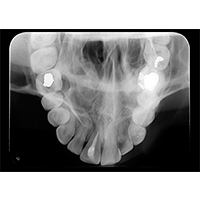

Oclusal